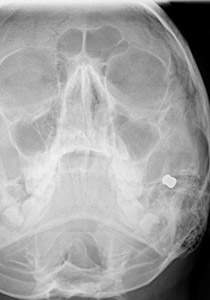

أصيب طالب بريطاني بطلقة نارية في وجهه، الأمر الذي يهدده بالحرمان من التبسم نتيجة لتضرر الأعصاب الرئيسية في وجهه. وكان الصبي "جوردن وينستانلي" (13 عاما) يسير مع مجموعة من أصدقائه عندما أطلق عليه شخص متخفٍ وسط الأشجار النار، فسقط على الأرض والدماء تنهمر من وجهه.

وعلى الفور تم نقله إلى المستشفى حيث خضع لعملية جراحية استمرت 3 ساعات، بحسب صحيفة "ديلي ميل" البريطانية.

وأخبر الأطباء والدي الصبي أنه قد لا يستطيع التبسم بعد ذلك نتيجة لتضرر الأعصاب الرئيسية في خده وفمه، ولذلك تعيش الأسرة حالة انتظار مؤلم لمعرفة إذا ما كان الطفل سيستطيع أن يستعيد ابتسامته أم لا.

وأضافت: "كان من الممكن أن يفقد جوردون عينه لو ارتفعت الرصاصة عدة سنتيمترات فقط. كما كان من الممكن أيضا أن تخترق عنقه، فتؤدي لمقتله.. كان هجوما غير مبرر".